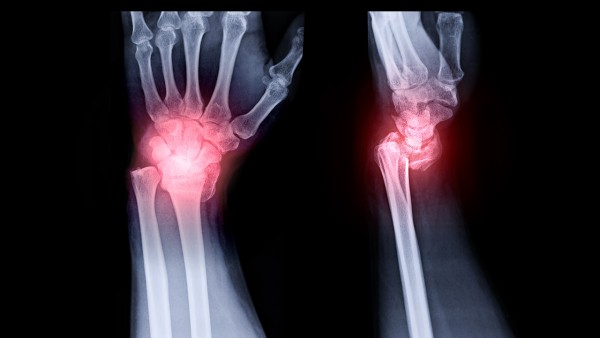

来氟米特片(爱若华)本品为白色薄膜衣片,去膜衣为白色。适用于成人类风湿性关节炎,可改善病情。